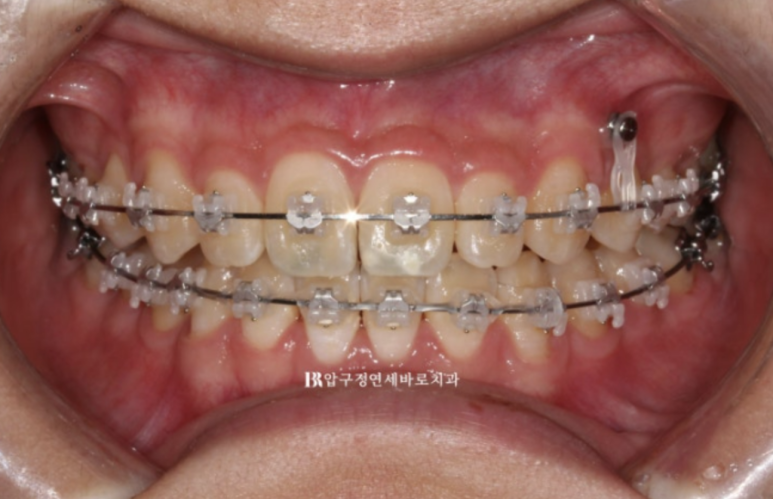

클리피씨로 교정하기를 원하셨고 치료 목표는 옥니와 과개교합의 개선 앞니 높낮이 조절로

앞니 노출도 개선.

편평한 입매 개선으로 입술 볼륨감을 회복합니다.

여기서 환자분의 요구 한가지는 한쪽 송곳니가 더 내려와 보이니 수평을 맞춰주세요 까지입니다.

23.07

내려와 있는 송곳니쪽에 미니스크류를 심어 교합평면을 맞추고

앞니에 파란색 레진 부분 바이트 블럭을 올려서 과개교합 개선과 소구치 정출을 도모했습니다.